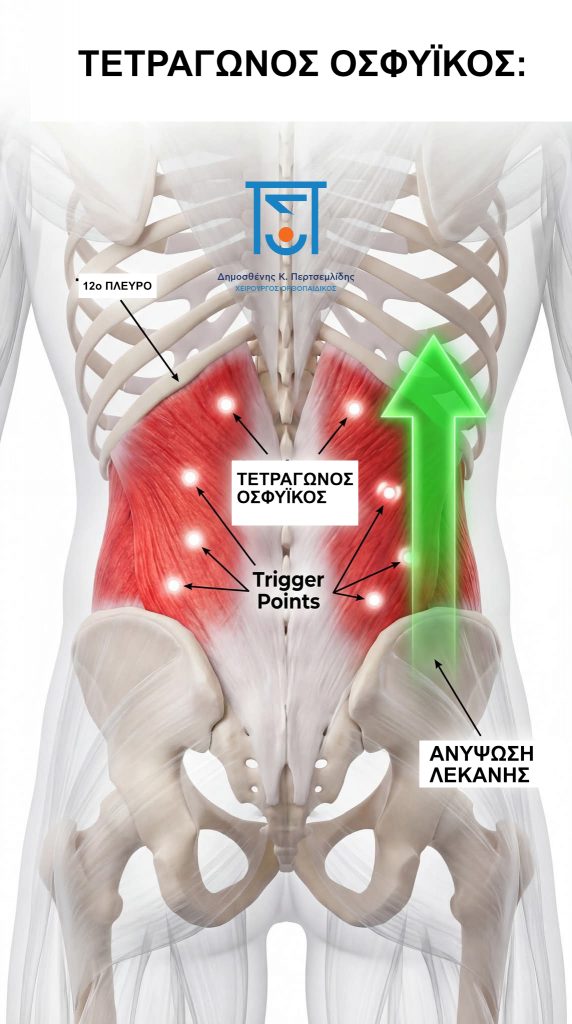

Όταν κάθεστε άνισα, κουβαλάτε μια βαριά τσάντα στον έναν ώμο ή κοιμάστε σε μια στριμμένη θέση, η μία πλευρά του Τετράγωνου Οσφυϊκού σας, υπερλειτουργεί. Αναπτύσσει πυκνά σημεία ενεργοποίησης (οι λαμπεροί λευκοί κόμποι στην εικόνα) και γίνεται απίστευτα ευερέθιστος.

Αυτός ο σπασμός δημιουργεί έναν μηχανικό εφιάλτη. Ο τετράγωνος Οσφυϊκός πιάνει σφιχτά το χαμηλότερο πλευρό και τραβάει βίαια προς τα πάνω στη μία πλευρά της λεκάνης σας (που φαίνεται από το πράσινο βέλος). Ο γοφός σου είναι ανεβασμένος, η οσφυϊκή σου στήλη συμπιέζεται πλάγια και οι γύρω αρθρώσεις είναι κλειδωμένες. Δεν αισθάνεστε μια σπασμένη σπονδυλική στήλη, αισθάνεστε τη συντριπτική δύναμη ενός μυϊκού σπασμού που προσπαθεί απεγνωσμένα να σας προστατέψει.